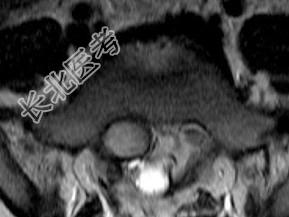

- 单项选择题男,8岁, 左髋疼痛,跛行1月余, 结合MRI检查,最可能的诊断是 ( )

A、骶部神经鞘瘤

B、室管膜瘤

C、神经纤维瘤

D、脊膜瘤

E、脊髓空洞症